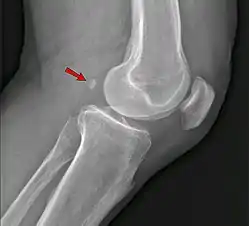

Os trigonum

The os trigonum or accessory talus represents a failure of fusion of the lateral tubercle of the posterior process of the talus bone. Is estimated to be present in 7–25% of adults.[17] It can be mistaken for an avulsion fracture of lateral tubercle of talus (Shepherd fracture) or a fracture of the Stieda process. In most cases, Os Trigonum will go unnoticed, but with some ankle injuries it can get trapped between the heel and ankle bones which irritates the surrounding structures, leading to Os Trigonum Syndrome.[21]